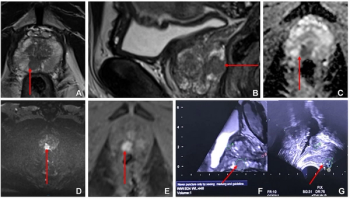

Reportedly the first FDA-approved PSMA PET agent with proprietary radiohybrid technology, POSLUMA can be utilized for positron emission tomography (PET) scans of prostate-specific membrane antigen (PSMA) positive lesions in men with prostate cancer and suspected metastasis, and those with suspected prostate cancer recurrence based on an elevated serum prostate-specific antigen (PSA) level.